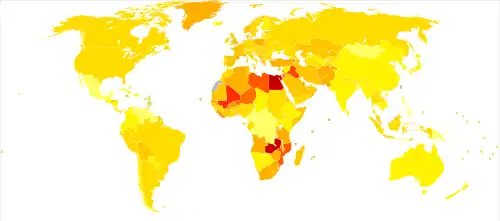

Around 500,000 people are diagnosed with bladder cancer each year, and 200,000 die of the disease.[17] This makes bladder cancer the tenth most commonly diagnosed cancer, and the thirteenth cause of cancer deaths.[56] Bladder cancer is most common in wealthier regions of the world, where exposure to certain carcinogens is highest. It is also common in places where schistosome infection is common, such as North Africa.[56]